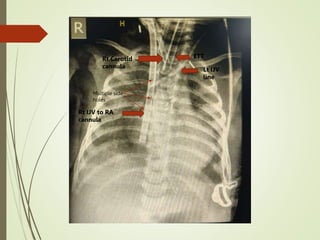

Rt IJV to RA

cannula

Rt Carotid

ETT

Lt IJV

line

Multiple side

holes

Rt IJV toRA cannula Rt Carotid cannula ETT Lt IJV line Multiple side holes